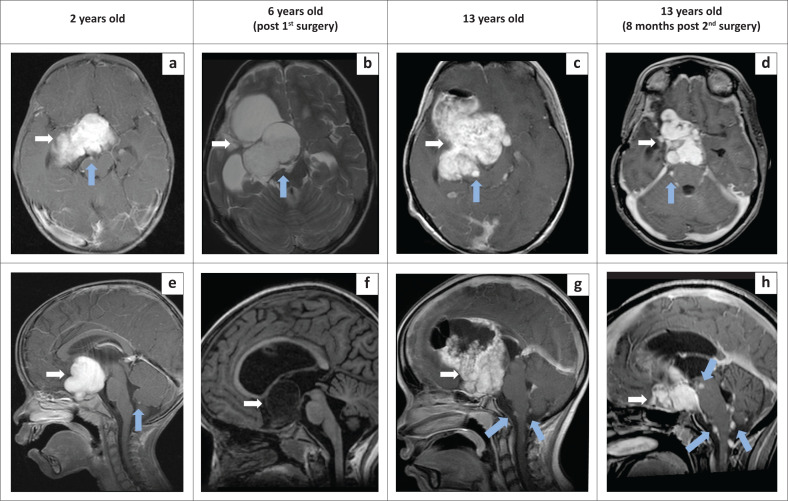

Leptomeningeal dissemination is a rare manifestation of pilocytic astrocytoma. It may occur with higher-grade tumours like medulloblastoma, ependymoma and high-grade glioma, but is extremely rare with low-grade glioma. There has been a growing number of reported cases documenting leptomeningeal dissemination of pilocytic astrocytoma in the medical literature.

Contribution: Description of a World Health Organization (WHO) Grade I suprasellar pilocytic astrocytoma with leptomeningeal dissemination in the brain and spinal cord which showed progression of the leptomeningeal nodules without tumour upgrading on long-term follow-up.